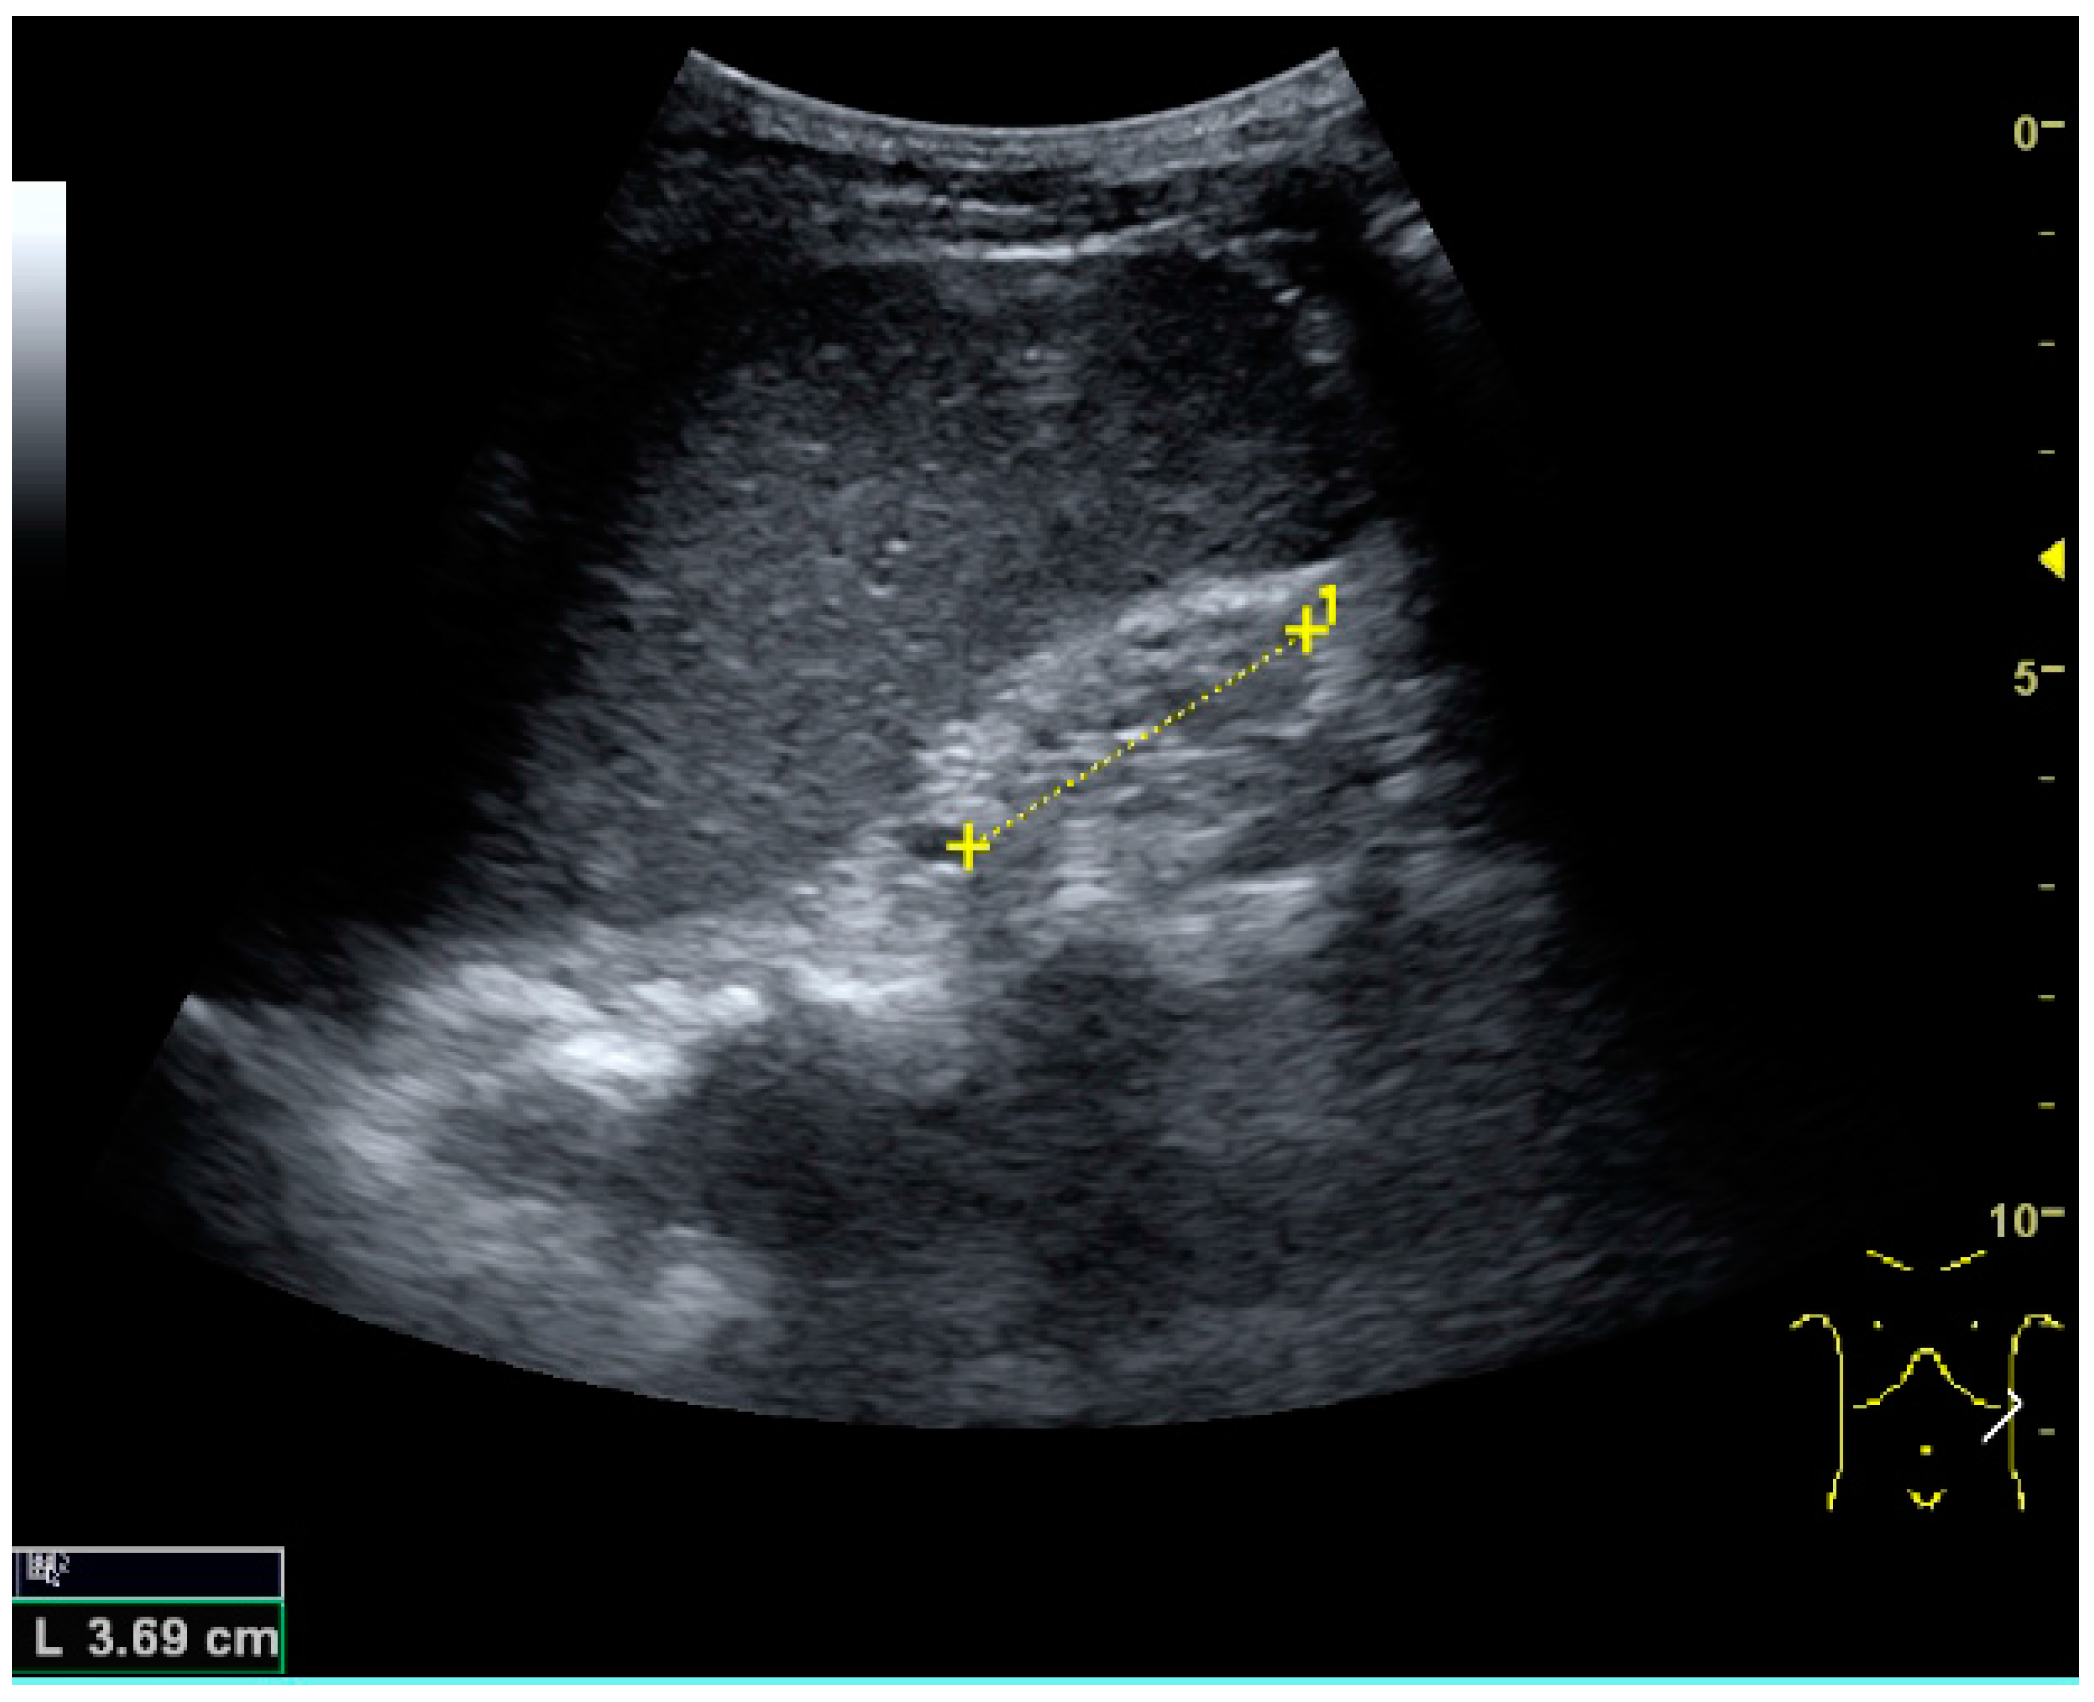

Complex cysts can have membranes dividing the fluid-filled center with internal echoes, calcifications or irregular thickened walls. The complex cyst can be further evaluated with Doppler US, and for Bosniak classification and follow-up of complex cysts, either contrast-enhanced ultrasound (CEUS) or contrast-enhanced computed tomography (CT) are used (Figure 6) [14,15]. The Bosniak classification is divided into four groups going from I, corresponding to a simple cyst, to IV, corresponding to a cyst with solid parts and an 85%–100% risk of malignancy [13,16].

Figure 6. Complex cyst with thickened walls and membranes in the lower pole of an adult kidney. Measurements of kidney length and the complex cyst on the US image are illustrated by ‘+’ and dashed lines.